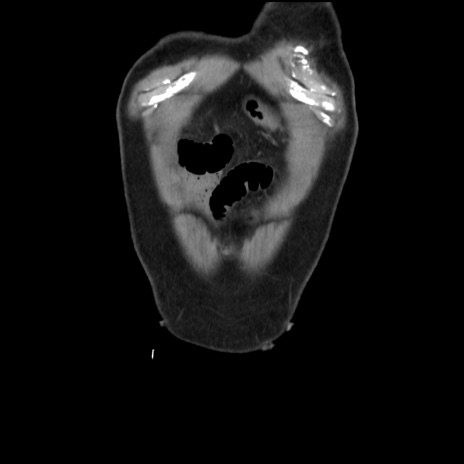

症例16(冠状断像)

横断像